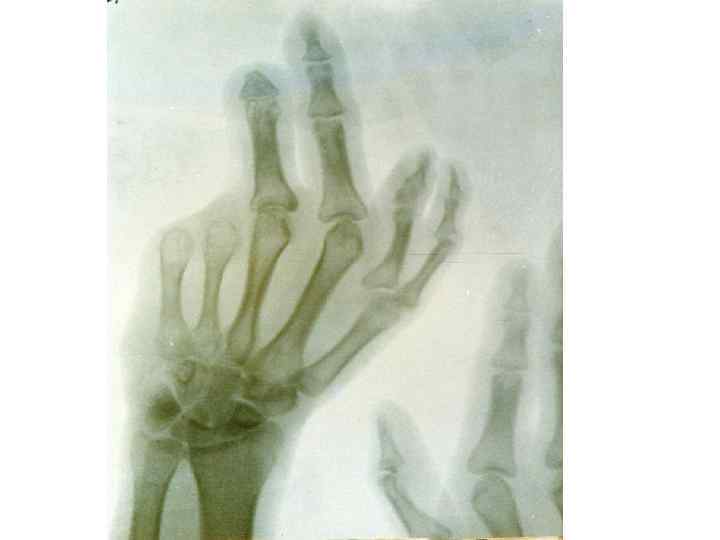

Омыртқалардың дамуының варианттары және аномалиялары 1 -омыртқалардың доғасының аномалиялары: -оң және сол жақ доғалардың біркіпеуі -доғалардың омыртқа денесімен бірікпеуі -омыртқа доғасының жетілмеуі немесе оның жоқ болуы 2 -омыртқалардың өсінділердің аномалиялары: -қосымша өсінділер -қылқан өсінділерінің бөліктенуі -буын өсінділерінің жетілмеуі және деформациясы 3 -омыртқалардың денесінің деформациясы 4 -омыртқалардың әрбір бөліктеріндегі, олардың сандары не көбейіп, не азайып өзгеруі • 5 -люмбализация • 6 -сакрализация • 7 -омырқалардың көптеген синостоздары • • •

8 -сколиоз 9 -омыртқалардың доғаларының бірікпеуі 10—спондилез Атавистикалық белгілер: 1 -күрең тәрізді тері өсіндісі 2 -құйымшақ омыртқаларының көп болуы 3 -күрең тәрізді өсінділер. Олар жұмсақ тіндерден тұрады да, терімен жабылады. Адам қартайған кезде омыртқалар омыртқа арасындағы дискалардың және олардың пішіндері өзгеруіне байланысты қозғаласы нашарлайды: олар серпінділігін жоғалтып үлкен кеуде қисығын түзеді – кәрілік қисығы.